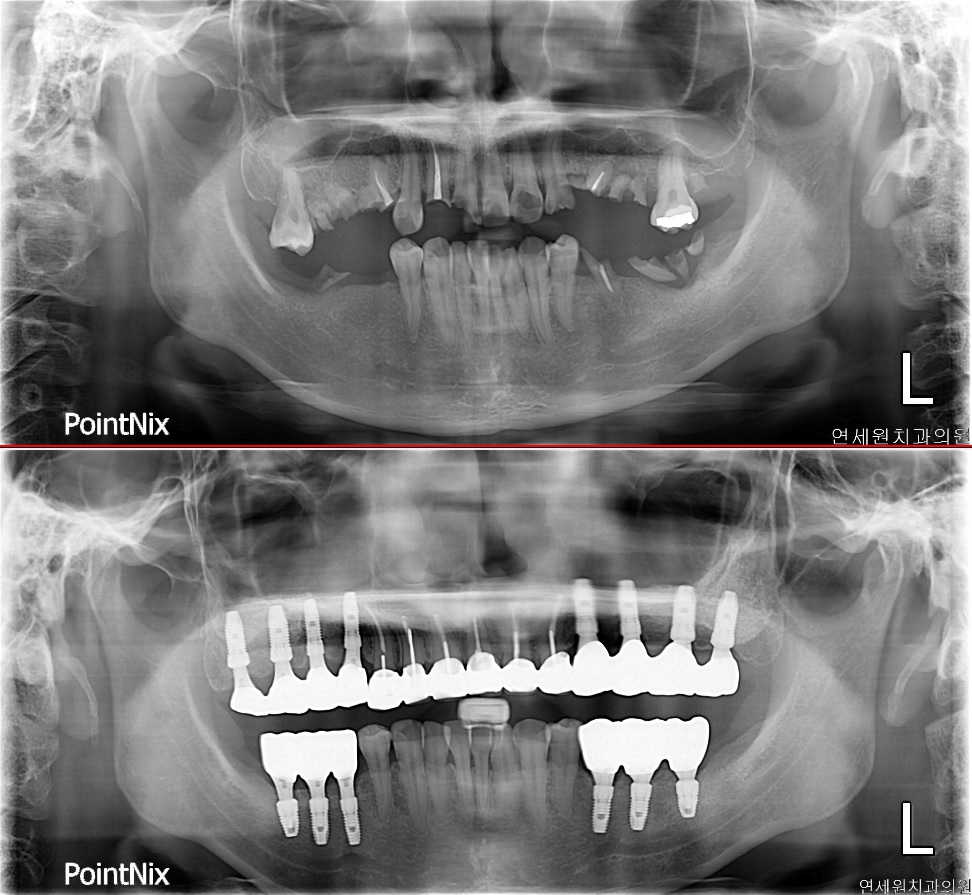

연세원치과의원

아산시에서 12년 동안 👴👵 어르신들의 치아 건강을 지켜온 연세원치과의원입니다. 구강 악안면외과 전문의 원장님이 임플란트 수술과 사랑니 발치를 특히! 👍 잘합니다. 과잉 진료 없이, 정직하게 진료하니 믿고 찾아주세요. 🙏

👍 꼼꼼한 진료와 친절한 서비스! 임플란트, 신경 치료, 잇몸 치료까지! 어르신들의 다양한 치과 고민을 해결해 드립니다. 💪